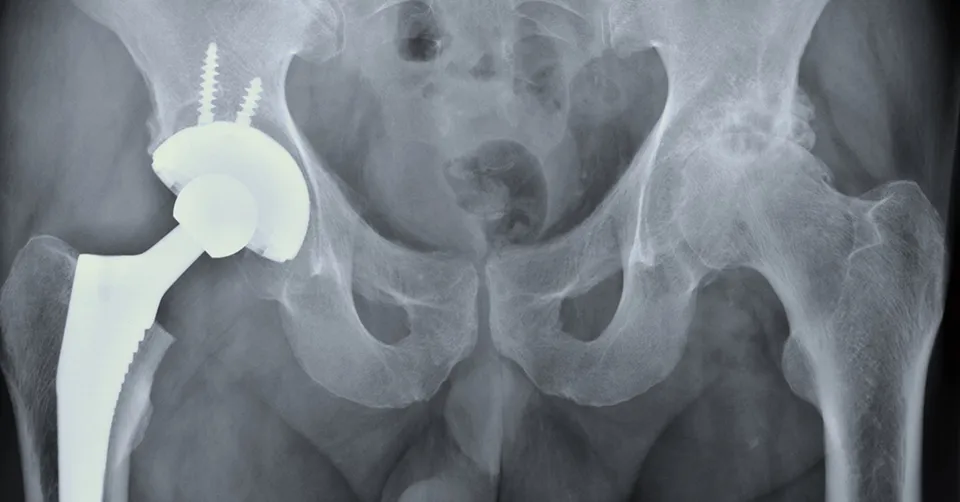

تتكون مفاصل الورك الصناعية عادةً من أربعة مكونات رئيسية، والتي يمكن تصنيعها من مواد مختلفة:

1. الساق (Femoral Stem): يتم إدخاله في عظم الفخذ. غالبًا ما يكون مصنوعًا من سبيكة التيتانيوم أو الكوبالت-كروم.

2. الكرة (Femoral Head): تركب على الساق، وتُصنع من المعدن أو السيراميك.

3. الكوب الحُقِّي (Acetabular Cup): يتم تثبيته في عظم الحوض. غالبًا ما يكون مصنوعًا من التيتانيوم.

4. البطانة (Liner): تُوضع داخل الكوب الحُقِّي، وهي الجزء الذي يحتك بالكرة. تُصنع من البولي إيثيلين، السيراميك، أو المعدن.

تُحدد أنواع المفاصل الصناعية بناءً على المواد المستخدمة في الأسطح الاحتكاكية (الكرة والبطانة).

طرق تثبيت المفصل الصناعي

بالإضافة إلى المواد، تختلف المفاصل الصناعية أيضًا في طريقة تثبيتها بالعظم. يختار الجراح طريقة التثبيت بناءً على عمر المريض، جودة عظامه، ومستوى نشاطه.

تثبيت بالأسمنت العظمي (Cemented) يتم استخدام أسمنت عظمي (بوليمر) لتثبيت مكونات المفصل مباشرة بالعظم. يوفر ثباتًا فوريًا. ثبات فوري وممتاز، تعافي مبكر من الألم، مناسب للعظام الهشة. قد يتآكل الأسمنت بمرور الوقت، مما يؤدي إلى ارتخاء المفصل، قد يكون صعب الإزالة في جراحات المراجعة. كبار السن، ذوو العظام الضعيفة (هشاشة العظام).

تثبيت غير أسمنتي (Uncemented/Press-Fit) تتميز مكونات المفصل بسطح خشن أو مطلي بمادة تسمح للعظم الطبيعي بالنمو عليها ومعها بمرور الوقت، لتثبيت المفصل بشكل بيولوجي. تثبيت طويل الأمد يعتمد على نمو العظم، مثالي للمرضى الأصغر سنًا والذين يتمتعون بعظام جيدة. يتطلب عظامًا ذات جودة عالية للنمو، قد يتأخر التعافي من الألم قليلًا، خطر أقل للارتخاء المبكر. الشباب، المرضى النشطون، ذوو العظام الجيدة.

تثبيت هجين (Hybrid) يجمع بين الطريقتين: غالبًا ما يتم تثبيت الساق بالأسمنت، بينما يتم تثبيت الكوب الحُقِّي بدون أسمنت (غير أسمنتي). يجمع بين مزايا الطريقتين، حيث يوفر الثبات الفوري للساق مع التثبيت البيولوجي طويل الأمد للحُق. لا يوجد عيوب رئيسية، خيار شائع وفعال. حالات معينة يحددها الجراح، غالبًا لمرضى متوسطي العمر أو كبار السن النشطين.